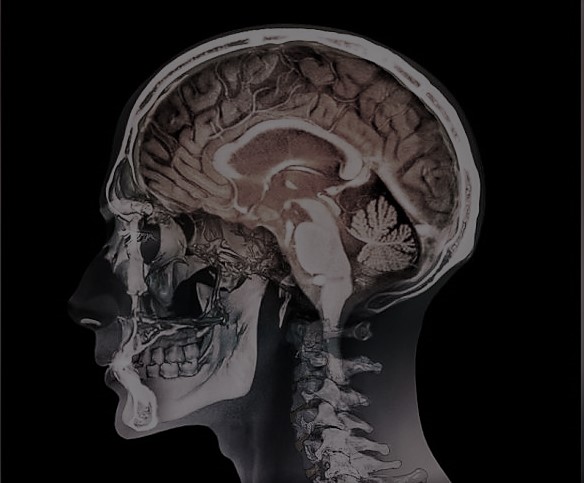

Le cabinet intervient exclusivement en matière de dommages corporels, notamment liés aux accidents médicaux. Il met à votre service son expertise pointue et sa longue expérience pour indemniser vos séquelles qui découleraient d’une erreur médicale, d’une infection nosocomiale ou encore d’un « aléa thérapeutique ».

Les victimes d’erreurs médicales sont des gens blessés. Ils sont mutilés physiquement mais aussi moralement. Ils perdent confiance dans le système de soin qui à défaut de les soigner a parfois aggravé leur état. C’est pourquoi, le Cabinet s’inscrit dans une démarche d’accompagnement qui va au delà de la simple prestation juridique. A titre d’exemple, nous n’hésitons pas à nous déplacer directement chez la victime pour lui offrir notre prestation si son état de santé le nécessite. L’avocat informe la victime de manière claire, une fois son dossier étudié, des voies de recours qui lui sont offertes, des chances de succès et du déroulement de la collaboration jusqu’à son terme.